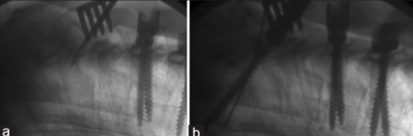

图12 CBT+TT+多棒固定

CBT+TT+多棒固定